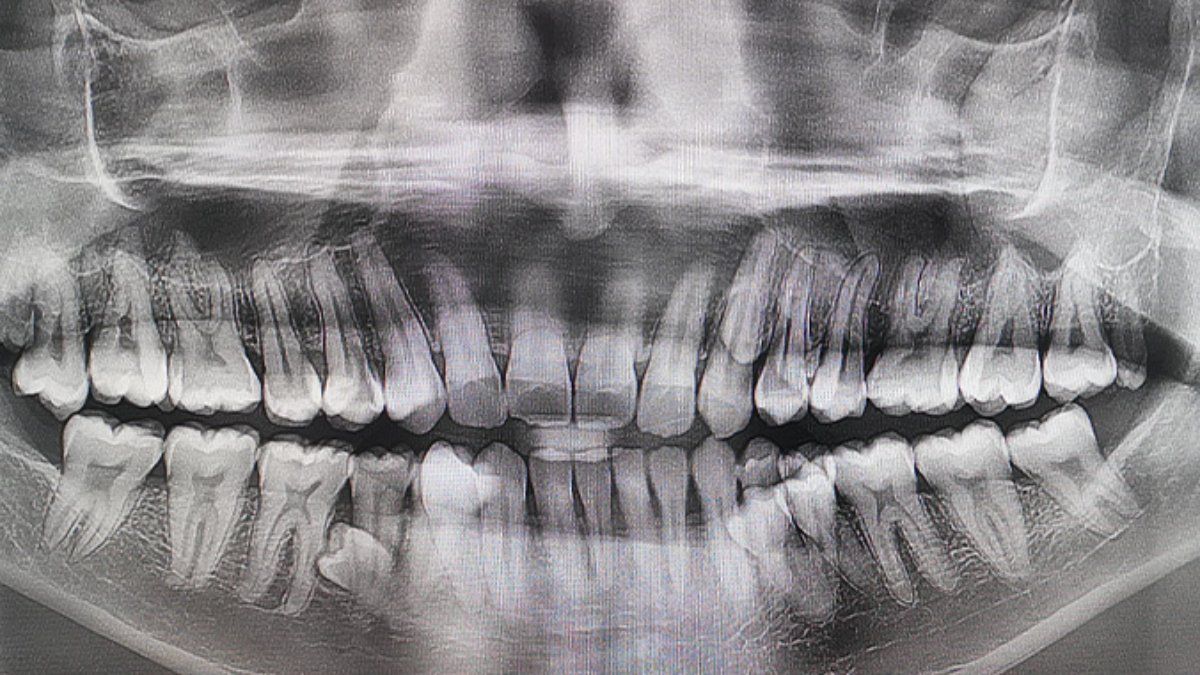

Чоловік має найбільшу кількість зубів у світі / Джерело: guinnessworldrecords

Чоловік із Малайзії здивував світ своєю незвичайною усмішкою – у його роті найбільша кількість зубів серед чоловіків у світі. Пратхаб Муніанді має 42 зуби, що на 10 більше, ніж у середньостатистичної людини, яка зазвичай має 32.

Його рекорд офіційно підтвердили у 2023 році після обстеження двома стоматологами. Цікаво, що лікарі також виявили ще два зуби, які поки не прорізалися. Пратхаб, який працює інженером у нафтово-газовій галузі, розповів, що вперше звернув увагу на незвичайну особливість у 2021 році під час сімейного чаювання. “Я сказав родині, що мені здається, ніби у мене ростуть зайві зуби. Ми разом їх порахували й виявили, що на той момент у мене було 38 зубів,” – пригадує він.